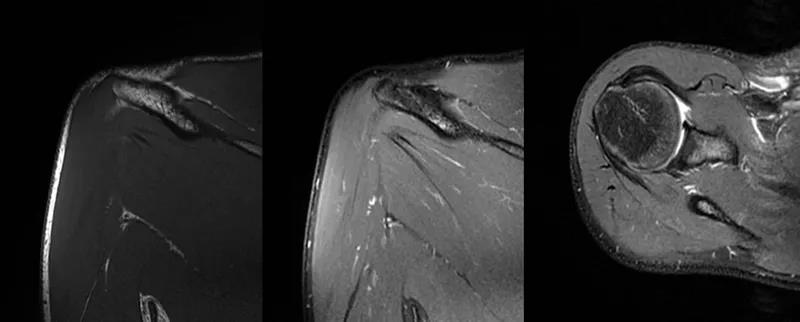

2、MRI检查MRI目前是诊断肩袖疾病中最常用的检查,可以直观的观察肩袖肌腱。

图21 斜冠状位(临床常用)a.T2,b.T1

图22 斜矢状位 a.冈上肌出口,肩袖诊断不如斜冠状位;b.冈上肌及肌腹脂肪浸润成度,评估手术与否

图23 横断位a.正常肩胛下肌;b.肩胛下肌损伤

图24 a.肩袖全层撕裂;b.正常MRI

图25 巨大肩袖损伤(冈上肌)